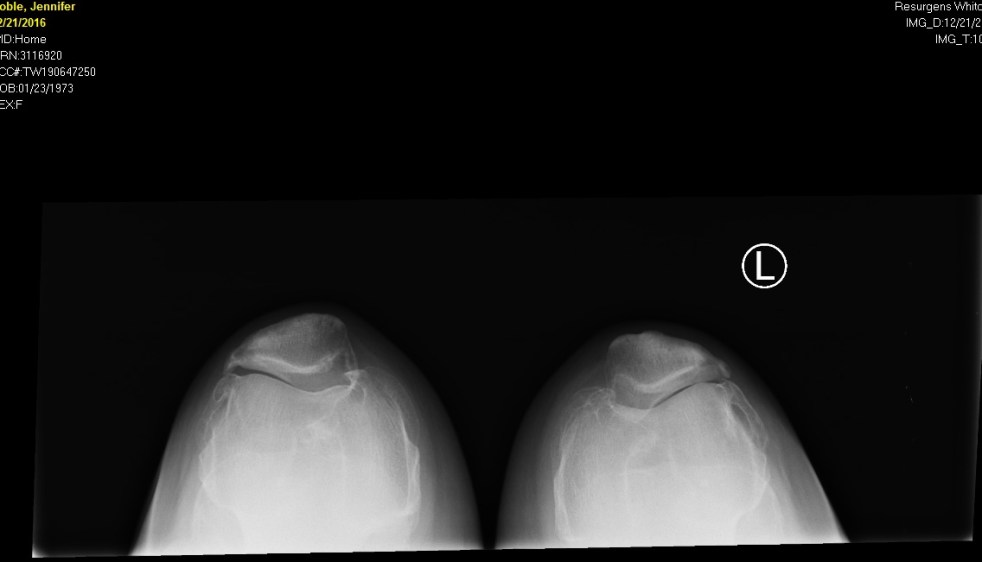

I can’t exactly pinpoint the injury that caused me to go from running 10+ miles of intervals to barely being able to walk down a hallway.  But the timeline goes something like this: 10/23:  Completed Atlanta 10 Miler.  15:03mm pace. Finished sore, but able to walk. 10/29:  Completed a 5 mile long run.  13:25mm pace.  Zero issues. 11/4:… Continue reading My injury